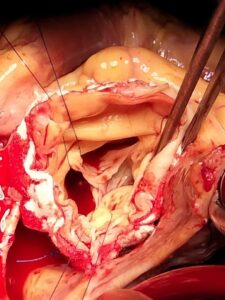

There are several approaches to complex aorta surgery, depending on the specific problem. The surgery is typically performed by a cardiovascular surgeon and can be done in different ways: